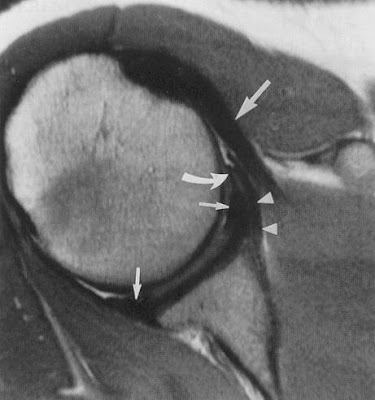

MRI Scan of shoulder showing labral injury